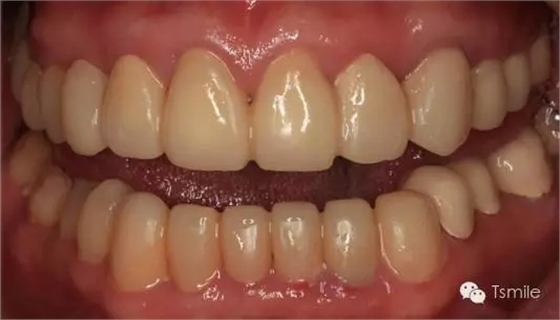

前兩個(gè)美學(xué)分析和美學(xué)表達(dá)過程已經(jīng)確定了患者滿意的最終的美學(xué)修復(fù)設(shè)計(jì),也就是已經(jīng)確定了最終修復(fù)體的形態(tài)、大小、排列、牙齦曲線等各種美學(xué)參數(shù),美學(xué)實(shí)現(xiàn)就是復(fù)制前面已經(jīng)確定的美學(xué)設(shè)計(jì)的過程,包括牙體預(yù)備、印模制取、修復(fù)體制作、修復(fù)體試戴粘接等過程。

例如面對一個(gè)牙列重度磨耗的美學(xué)修復(fù)患者,我們首先根據(jù)患者主訴和美學(xué)檢查形成美學(xué)設(shè)計(jì),然后通過數(shù)碼圖像表達(dá)美學(xué)設(shè)計(jì)思想,制作診斷蠟型,口內(nèi)制作診斷飾面,更加真實(shí)地表達(dá)美學(xué)設(shè)計(jì)。根據(jù)患者的要求和口內(nèi)試戴情況調(diào)改診斷飾面,最終確定美學(xué)修復(fù)設(shè)計(jì),即最終修復(fù)體的各種美學(xué)參數(shù)。接下來就是美學(xué)實(shí)現(xiàn)過程,在診斷飾面上進(jìn)行精確地牙體預(yù)備,制取印模和工作模型,技師按照最終診斷飾面的形態(tài)、大小和排列制作最終美學(xué)修復(fù)體,最后完成修復(fù)體粘接。

圖6:最終修復(fù)體完成 來源于tsmlie